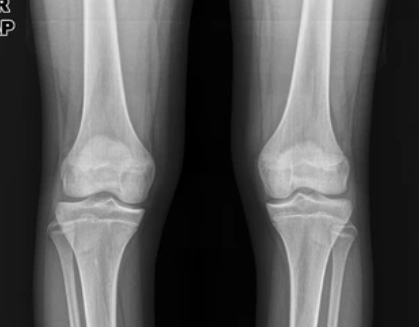

4. 전문가의 신체검사: 손목 및 다리 관절의 상태, 척추의 자세, 신체 비율 등을 평가하여 성장 가능성을 추정할 수 있습니다.